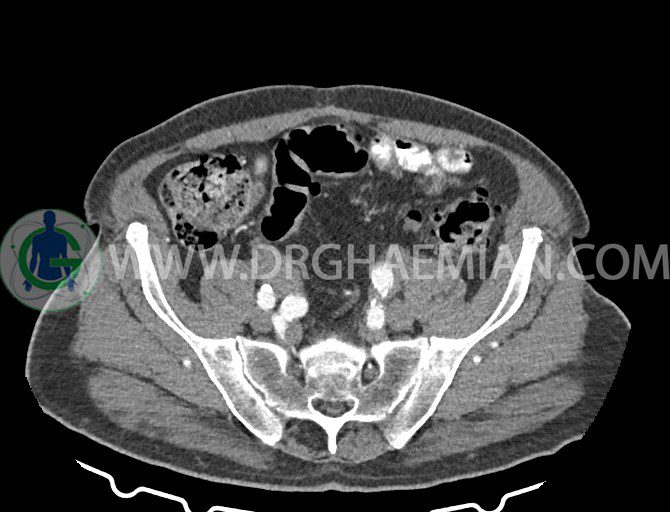

سی تی اسکن لگن یکی از روش های تصویربرداری با سی تی اسکن است. این روش با استفاده از تشعشعات تصاویر عرضی از ناحیه شکمی ایجاد میکند. در این کیس ديورتيكولوزيس، کیست های کورتیکال در هر دو کلیه، لنفادنوپاتی، کلسیفیکاسیون دیواره آئورت و شریان ایلیاک، تغییرات DJD ناحیه توراکولومبار و پروستات بزرگتر از عادی دیده می شود.

در سي تي اسکن اسپيرال شکم و لگن با و بدون کنتراست خوراکی و وريدی (مولتي ديدکتور 16 با مقاطع ظريف و بازسازي هاي ساژيتال و کرونال):

– کيست هاي کورتيکال ساده به قطر 5 mm تا 50 mm در کليه راست و به قطر 5mm تا 55 mm در کليه چپ

– کلسيفيکاسيون ديواره آئورت و شريان ها ايلياک همراه با نشانه هاي ترومبوز مورال در بيفورکاسيون ائورت با امتداد به پروگزيمال هاي شريان هاي ايلياک

لنفادنوپاتي به ابعاد mm 22 x 25 مجاور شريان ايلياک خارجي چپ و به ابعاد mm 17 x 28 مجاور شريان ايلياک خارجي راست

– پروستات به ابعاد mm 45 x 54، بزرگ تر از نرمال

مشهود است.